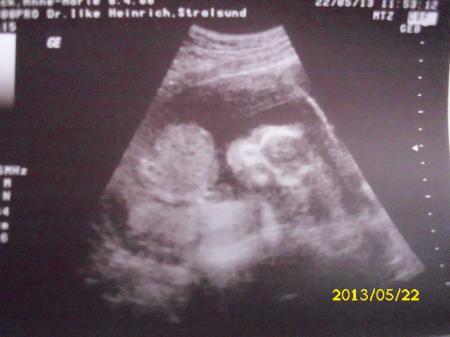

so ihr lieben ich bin endlich wieder zuhause. heute war mein freund mit dabei und er war so schön aufgeregt . ich bin erst zu der schwester rein wo blutdruck und so gemessen wurde. habe "bloß" 1,5 kilo zugenommen :-) danach habe ich das erste mal den herzschlag vom würmchen gehört das war so schön. . Der us an sich war echt toll. weil wir ihn diesesmal selber bezahlt haben hat sie sich ein bisschen mehr zeit genommen uns alles zu zeigen. vermessen ging leider nicht da krümel umhergesprungen ist wie ein wilder. Fand das so süß habe sogar geweint . das geschlecht dürft ihr heute mal selber raten. mein freund und ich sind einfach nur wunschlos glücklich

bild mit outing :-)

also ICH glaube es ist ein kleiner Junge *g wann kommt denn die Auflösung????

oje auf dem Bild kann ich GAR nix erkennen bin nur nach meinem Gefühl gegangen *g Jetzt bin ich ja mal gespannt was die anderen da so sehen

schön das alles super ist :) aber leider kann ich auch garnichts erkennen

Auf dem Bild erkennt man gar nichts. Aber so früh erkennbar ist es meist nur bei den Jungs.

Auch wenn man nicht viel erkennt, würde ich jetzt auch spontan mal auf einen tippen!!

Ein Mädchen . Alles gute :) richtig?

Hmm...also ich erkenne auch nichts Aber ich hab auch meistens bei meinen eigenen US-Bildern Probleme was zu sehen. Bin aber ja auch erst in der 14.Woche Also ich rate einfach mal und tippe auch auf einen Jungen

Ja es ist ein kleiner junge habe es aber auch erst zuhause auf dem us-bild richtig sehen können :-)